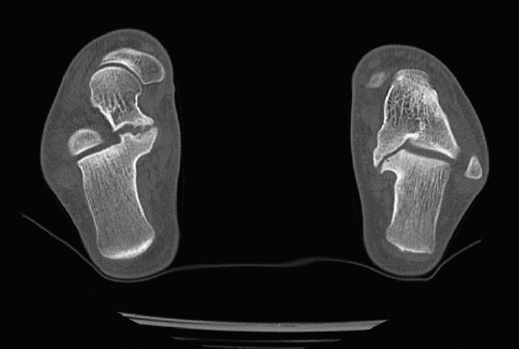

Figura 9. Pseudoartrosis subastragalina.

Se trata de un caso del Dr. Cuervas-Mons, publicado en Techniques in Orthopedics(15), acerca de un paciente varón de 54 años que acude a la consulta con dolor del retropié y deformidad en varo. Tras la valoración, se evidencia pseudoartrosis sintomática (Figura 9), por lo que se decide llevar a cabo tratamiento quirúrgico.

Se presenta un problema: la identificación del plano de pseudoartrosis es fácil de manera preoperatoria con el uso de imágenes; sin embargo, la identificación del plano de pseudoartrosis completo de manera intraoperatoria puede ser difícil, siendo necesario una resección ósea amplia y en ocasiones insuficiente.